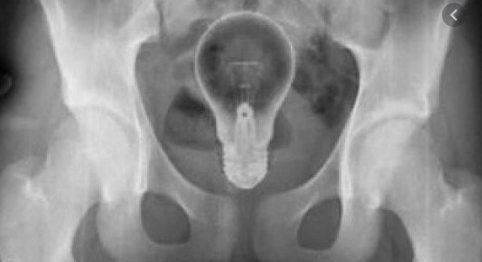

Pour faire simple, l'air, dans les poumons ou les intestins par exemple, va apparaitre très noir, et les métaux très blancs. (voir sur la photo).

(oui certaines personnes trouvent ça bien d'introduire des objets dans leur corps... pas de commentaire)